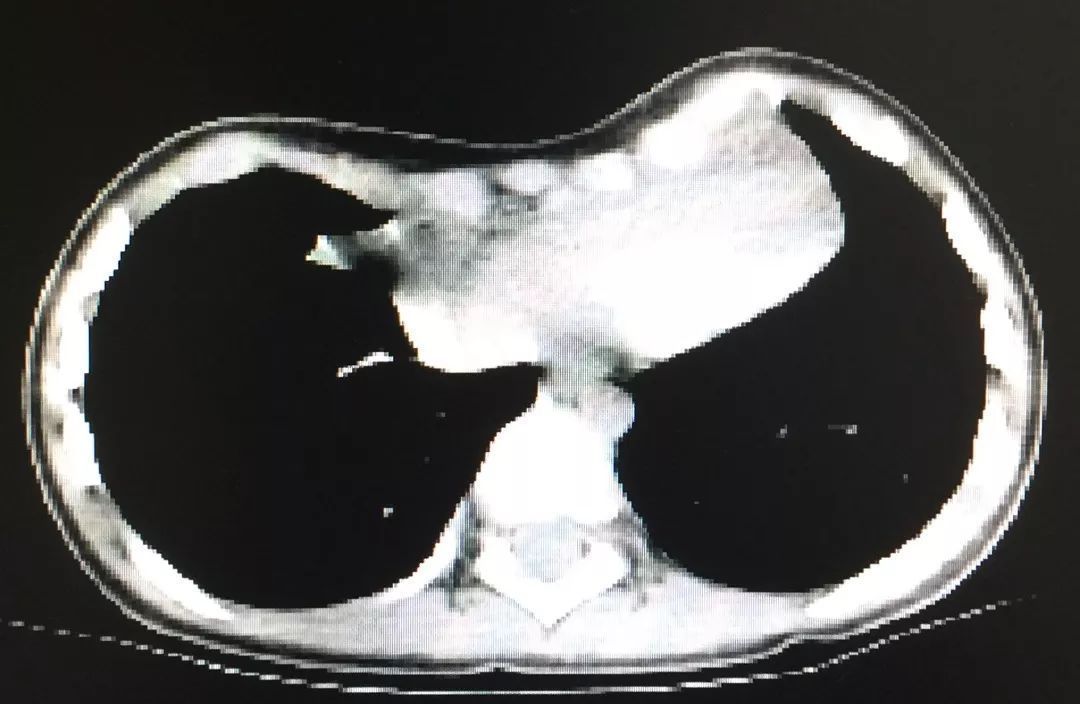

患儿入院后经检查,见前胸壁已呈严重漏斗状凹陷,胸部CT检查可见心脏已明显受压。医生表示,这种畸形必须要尽早接受手术治疗。

术前